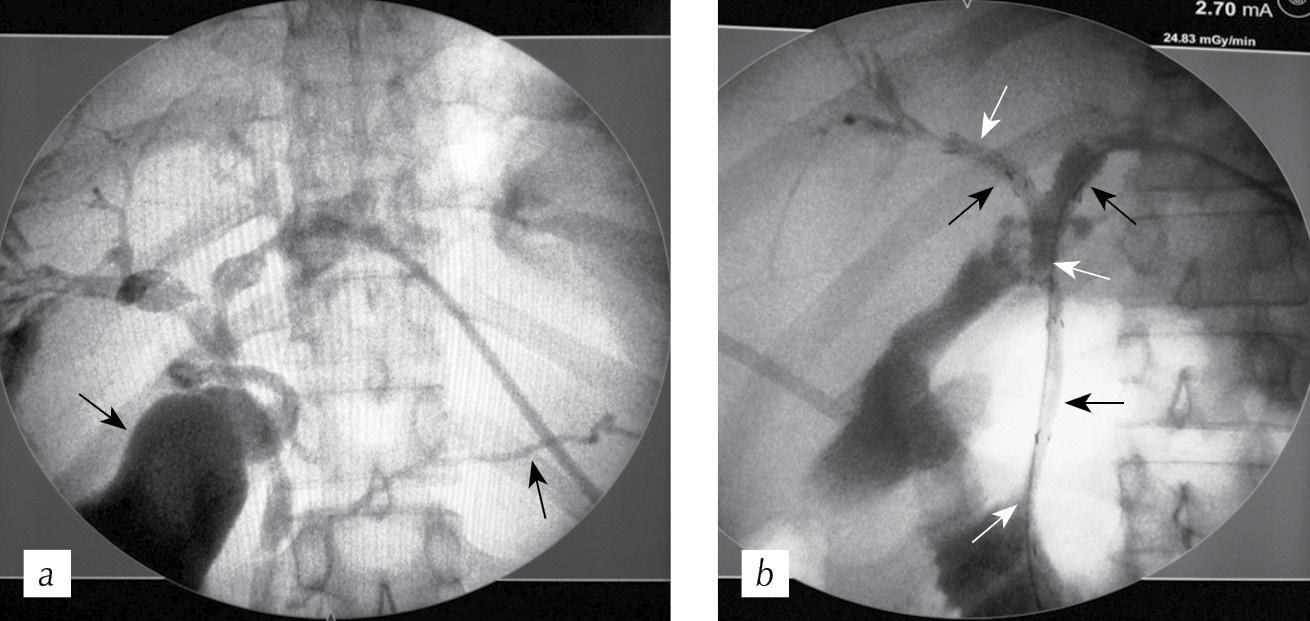

Clinical case

Patient M., 83 years old, was admitted with the primary diagnosis of gallstone disease, choledocholithiasis, and obstructive jaundice. He had a secondary diagnosis of coronary heart disease, abdominal compartment syndrome, angina of effort of functional class 3, ciliary arrhythmia, permanent form; hypertension stage III; chronic heart failure, degree IIIA, functional class 3; risk of cardiovascular complications 4; hepatic cirrhosis; cerebrovascular disease; disculator encephalopathy, degree II; chronic bronchitis; respiratory failure, degree I; benign prostatic hyperplasia, degree II; and chronic pyelonephritis, latent course. His condition after Billroth II resection of the stomach in 1979, indicated that he had postoperative ventral hernias, degenerative and dystrophic diseases of the spine, and osteochondritis of the spine. The patient’s history reveals that in 2011, he was operated on in one of the hospitals in St. Petersburg for a laparotomy, choledocholithotomy, and drainage of the CBD according to Kehr. In 2014, the patient underwent a mini-laparotomy, choledocholithotomy, and drainage of the CBD, according to Kehr. After the examination, transhepatic external-internal cholangio-drainage was performed, during which a stricture of the CBD terminal section was found, with calculus of 3.2 × 1.8 cm. After three weeks, the patient was repeatedly hospitalized in a planned manner, bougienage of the stricture of the terminal part of the CBD, percutaneous lithotripsy, and repeated drainage of the bile ducts were performed. After one month, the endoprosthetics of the bile ducts were performed (Fig. 3). No problems occurred during the postoperative period. The endoprosthesis was removed after two years and seven months; however, its replacement was never performed. The follow-up of this patient’ s case was performed for 10 months.

Fig. 3. Cholangiograms of the staged treatment of “major” recurrent choledocholithiasis: a — transhepatic external-internal cholangiodrainage; b — percutaneous lithotripsy, lithoextraction; c — endoprosthesis placement

Рис. 3. Холангиограммы этапного лечения «крупного» рецидивного холедохолитиаза: a — чреспеченочное наружно-внутреннее холангиодренирование; b — чрескожная литотрипсия, литоэкстракция; c — эндопротезирование